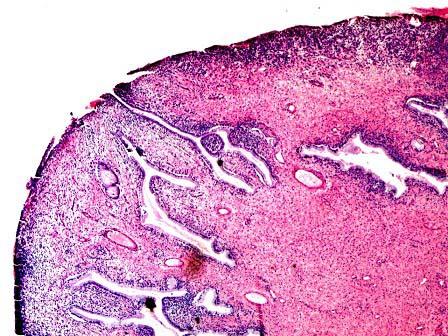

问题 女性,26岁,孕5周,药流手术后。妇科检查宫颈光滑,宫口突出一舌状小指甲大小物。显微镜下大部分为肉芽组织,其表面被覆少许鳞状上皮(如图)。最适当的诊断为 ( )

选项 A.慢性子宫颈炎 B.子宫颈息肉 C.子宫颈腺瘤 D.子宫颈平滑肌瘤 E.子宫颈鳞状细胞癌

答案 B